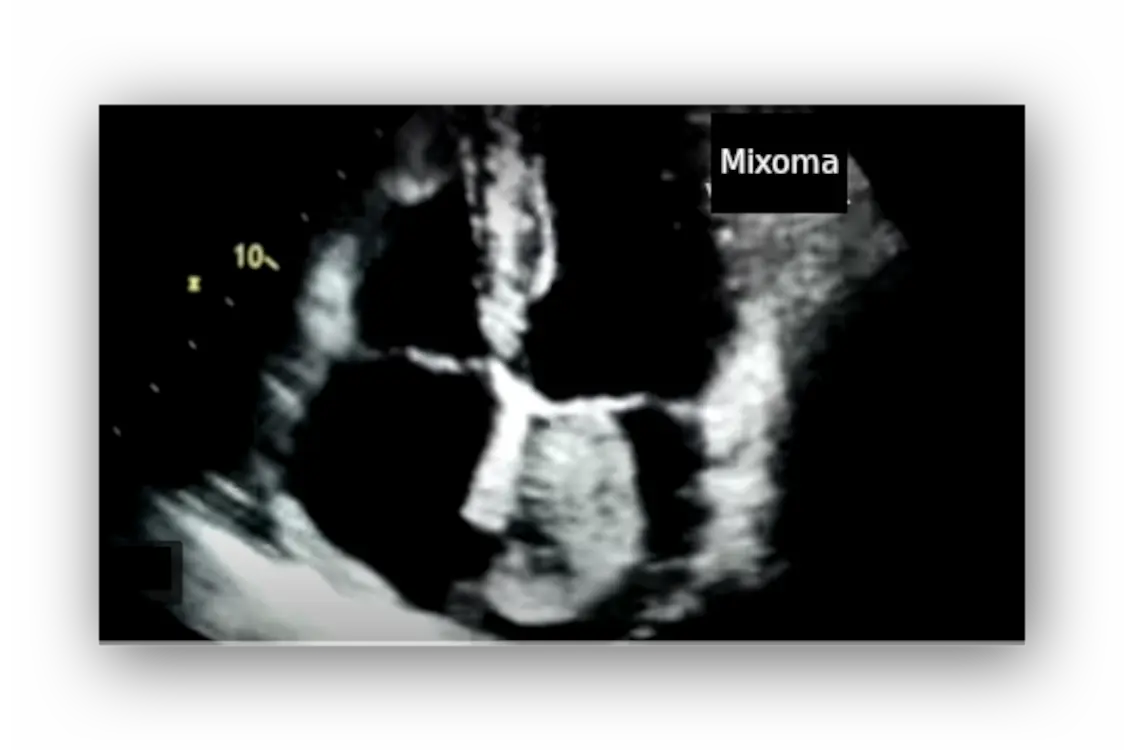

The most important diagnostic technique for diagnosing myxoma is an echocardiogram. The images obtained reveal a mass in one of the cardiac chambers, habitually in the left atrium. More than one mass is rarely found.

Myxomas are usually located in the left atrium, attached to the interatrial septum. They are typically spherical or oval, although sometimes they are polygonal or polypoid. The mass may be homogeneous or present cystic, hemorrhagic, or calcified areas.

Although myxomas may be fairly fixed, they are typically seen moving within the heart, sometimes entering the valve orifice with each cardiac contraction, eventually causing obstruction to blood flow.